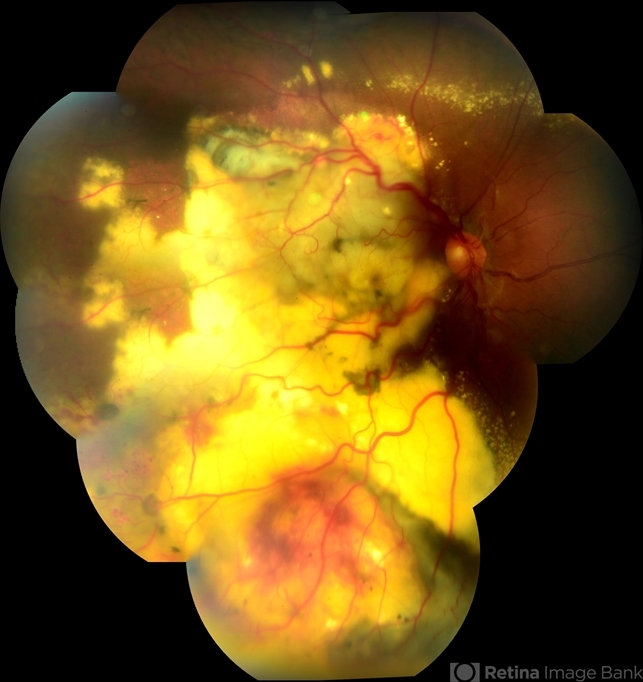

- Leber's miliary aneurysm, lipid exudation, massive lipid exudation

Fundus camera

Fundus camera Topcon TRC-50 DX, Imaginet 5.0, angle de 50 graus. Flash 36 / Mosaic with 11 images. - Description

- Male patient, 29 years old, with low vision in the right eye has 9 months. In the retinal mapping and color retinography examination, there were important fundoscopical alterations.